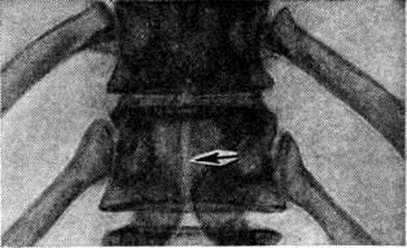

Локализация расщелины в теле или дуге позвонка может быть самой различной (рисунок 2). Рентгенологически легче распознаются расщелины, ориентированные в сагиттальной плоскости, которые лучше видны на рентгенограмме в прямой проекции. Расщелины в боковых отделах дуг и тел видны на рентгенограммах в боковой проекции, а иногда только на томограммах. При локализации в телах позвонков (spina bifida anterior) щель делит тело позвонка на две части, каждая из которых имеет на рентгенограмме в прямой проекции клиновидную форму. Чаще обе части тела позвонка расположены симметрично, напоминают по виду крылья бабочки — так называемый бабочковидный позвонок. Однако клиновидные части тела позвонка могут быть и асимметричными (рисунок 3). В процессе роста тела соседних позвонков приспосабливаются к форме аномальных позвонков.

Томограмма части поясничного отдела позвоночника при spina bifida anterior (прямая проекция): тела III и IV поясничных позвонков имеют широкие передние расщелины (указаны стрелками).